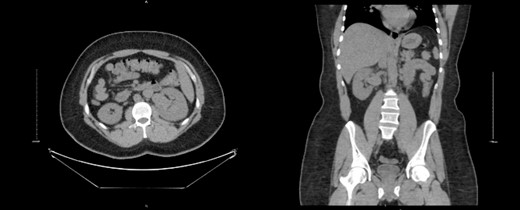

A 32-year-old male with no known chronic illnesses had a history of a motor vehicle accident five years ago, resulting in multiple bilateral rib fractures. An abdominal and pelvic CT scan conducted at the time did not reveal any other findings. The patient was admitted under the care of thoracic surgery for observation and pain management. After four years from the accident, the patient experienced intermittent right flank pain and made multiple visits to the emergency room. A CT scan of the kidneys, ureters, and bladder (CT KUB) was performed to rule out urolithiasis. The CT KUB showed multiple prominent structures with communication between the arterial and venous systems at the right renal hilum, suggestive of an intrarenal AVM with no apparent complications (Fig. 1). A CT run-off study confirmed the presence of an intrarenal AVM in the upper pole, measuring 2.9 cm (Fig. 2). The patient underwent angioembolization; however, multiple attempts at coil embolization failed due to the high risk of distal embolization. Subsequently, the patient underwent exploratory laparotomy for right AVF ligation. During the procedure, three AVF tracts were identified and ligated using clips. Prior to ligation, a thrill was palpable, but it was absent after the ligation. On the second postoperative day, a Doppler renal US was performed, which revealed patent right intrarenal arteries with normal resistive indices and normal peak systolic velocity in the right main renal arteries.

Run-off computed tomography angiography (CTA) showed right kidney hilum tortuous vascular arteriovenous communication of the arterial and venous system represents intrarenal AVM towards the upper pole measuring 2.9 cm.